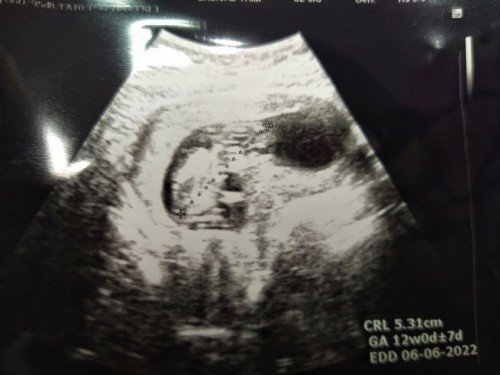

ซาวด์แล้วเจอน้องนั่ง

สอบถามแม่ๆซาวด์ตอน12Weekมีใครเจอน้องนั่งแบบนี้บางค่ะแต่คุณหมอบอกว่าปกติ#ใครมีประสบการณ์

ปกติคะ น้องสามารถเปลี่ยนท่าไปเรื่อยๆคะ ขึ้นอยู่ที่ว่าตอนซาวน์ เราจะเจอท่าไหน บ้านนี้เคยเจอนอนคว่ำหน้า